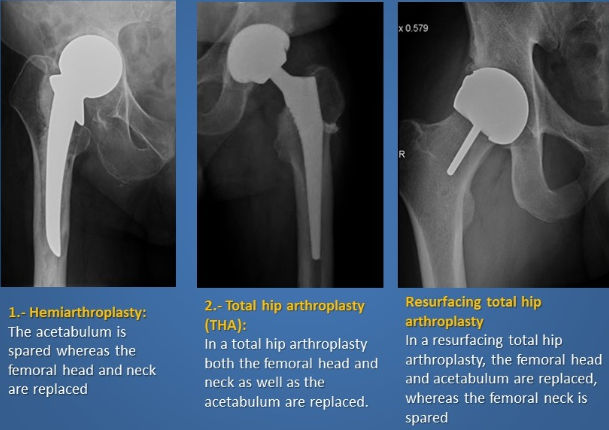

What do each of the following mean?

Total joint replacement

Hemiarthroplasty

Partial joint resurfacing

A

Replacing both articular surfaces of the joint

Replacing half of the joint

Replacing part of the joint surfaces e.g. only medial surfaces of the knee